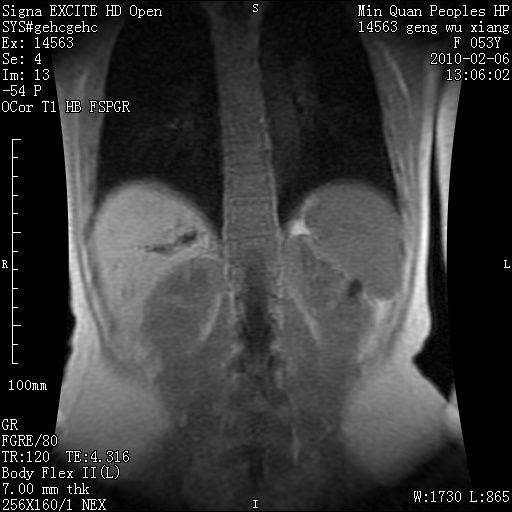

标题: MRI2762:胆道梗阻原因?

f,53y,全身黄染多日。

高位胆道梗阻 胆管癌可能性大

支持 高位胆道梗阻 胆管癌可能性大。